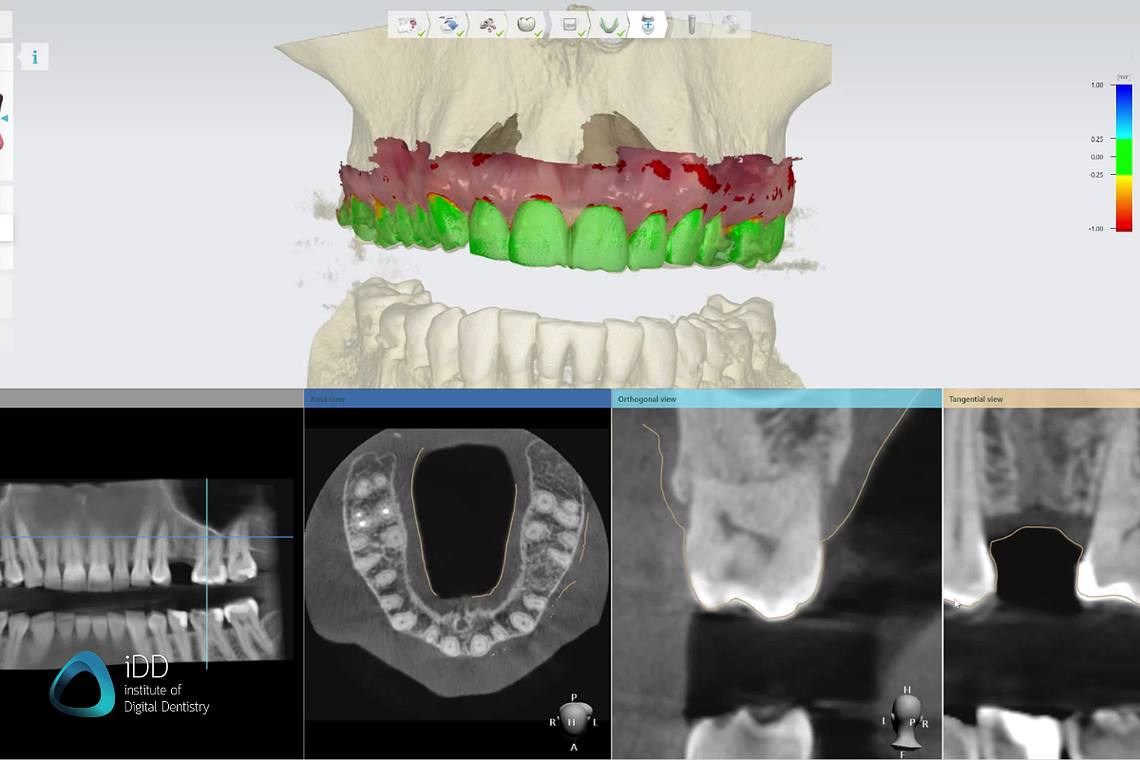

Patients’ CBCT scans with intraoral scans provides adequate information for safe and functional implant placement. Software: 3Shape Implant Studio.

CBCT scans enable precise implant planning by assessing bone quality and quantity, identifying vital anatomical structures (such as nerves and blood vessels), and determining the optimal implant size, angulation, and position.

CBCT scans help in planning complex restorative cases, including the evaluation of tooth and bone support, assessment of occlusal relationships, and fabrication of surgical guides for accurate prosthesis placement.